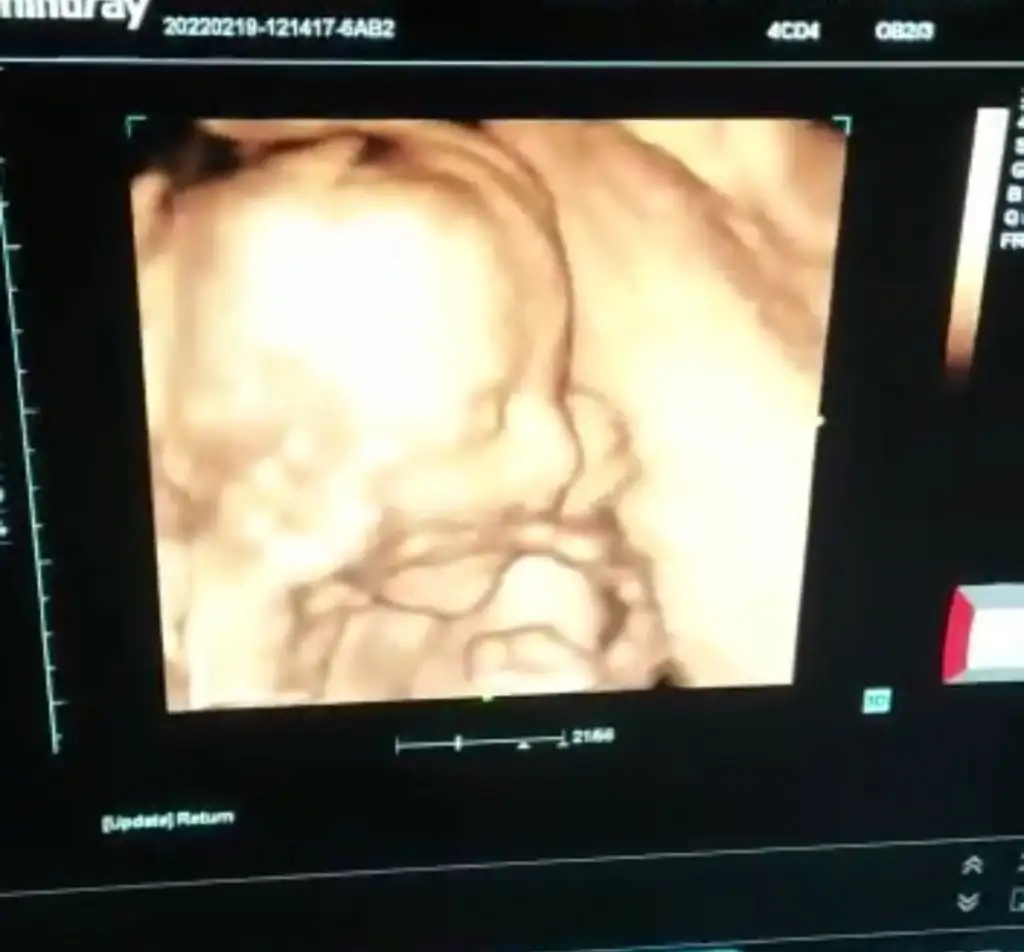

yoncambenim canim detaylı icin doktorum betatom a yönlendirdi bahcelievlerde yeri.doktor yönlendirdiği icin 700 TL dedi

21.haftadan 1-2 gun sonra bakiliyo dedi kadın.henuz randevu almadım ararım bir kac güne randevu oluştururum.pahali ama fiyatlar hep böyle sanırım en azından doktorumun tavsiye ettiği yer olsunHeeeee benim kuzenimde oraya gidiyo incirli caddesine yakın hatta , iyi ozman canım nezman gidicen

Aynenn canımm kuzemim 1100 tl demişti sen 700 dedim demekki kuzenim bana sallamış fiyatı21.haftadan 1-2 gun sonra bakiliyo dedi kadın.henuz randevu almadım ararım bir kac güne randevu oluştururum.pahali ama fiyatlar hep böyle sanırım en azından doktorumun tavsiye ettiği yer olsun